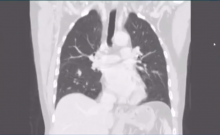

Minimally Invasive Complex Lung Resections [1]

Rene Petersen of Copenhagen University Hospital in Denmark describes his approach to difficult resections using a VATS approach. He uses several video clips to demonstrate his techniques.